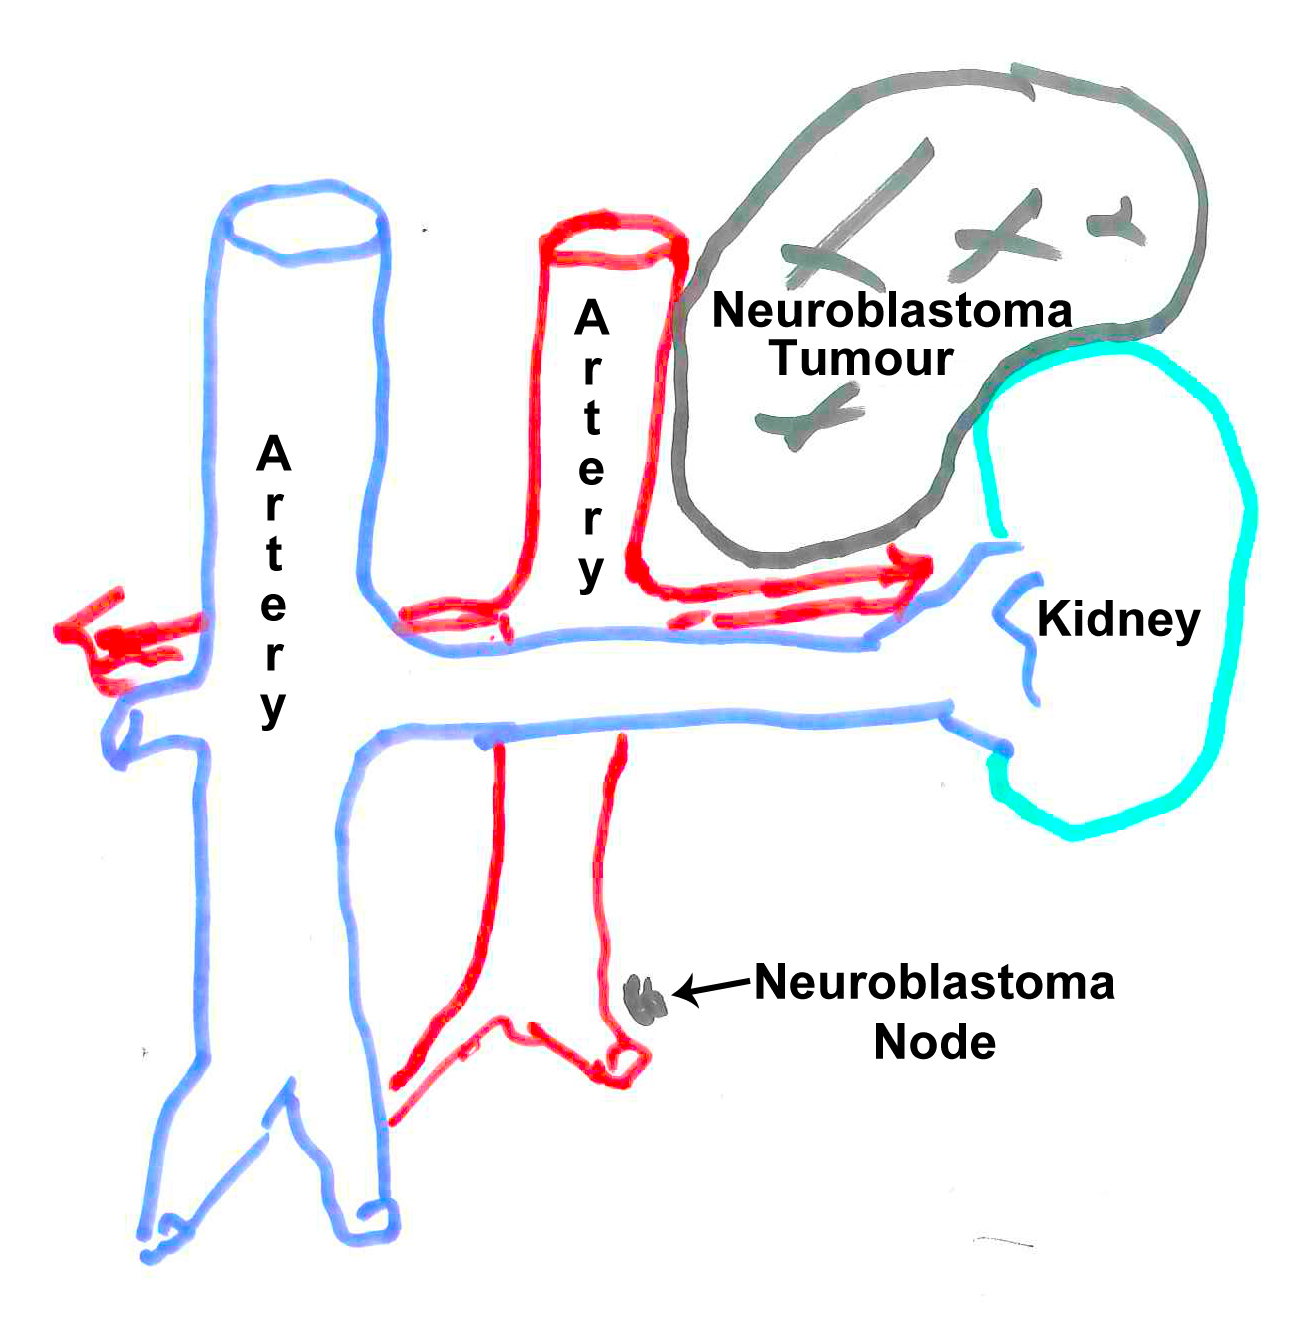

14:15-18:40 Laparoscopic Surgery removed the tumour and nodes near her artery. It was a clean removal and the tumour was taken out in one piece. Her kidney was pushed aside and partially encapsulated by the tumour but it seems it did not encroach into the kidney. The kidney could stay and a full recovery is expected. The surgeon inspected but did not find any nodes in pelvis area. The chemo has removed all the nodes. There were no complications.

07:00, met with oncology surgeon who confirmed that surgery is set for 21 October 2011. He explained that he did not expect any complications and that he is very happy with Kim's progress. He drew the picture above to explain that the Neuroblastoma node is very small and may be gone at the time of surgery, although he will still investigate the area during surgery. He also explained that he did not expect that Kim will loose her kidney. The tumour is close but did not seem to invade the kidney so she probably will not loose any part of it. While previously the tumour seemed to get too close to the arteries, now it looks very good and it will be a straight forward procedure for the surgeon. The procedure will take around 4 hours. She is planned to stay in hospital for post surgery recovery for 4 days and will probably be down and in bed for the first two. The last two days she is expected to become her active self again. Then off to home and following with next Chemos etc. The surgery date will only change if her blood levels are not good because of the prior chemo and any side effects. But it is expected she will be OK. She has been doing good so far.